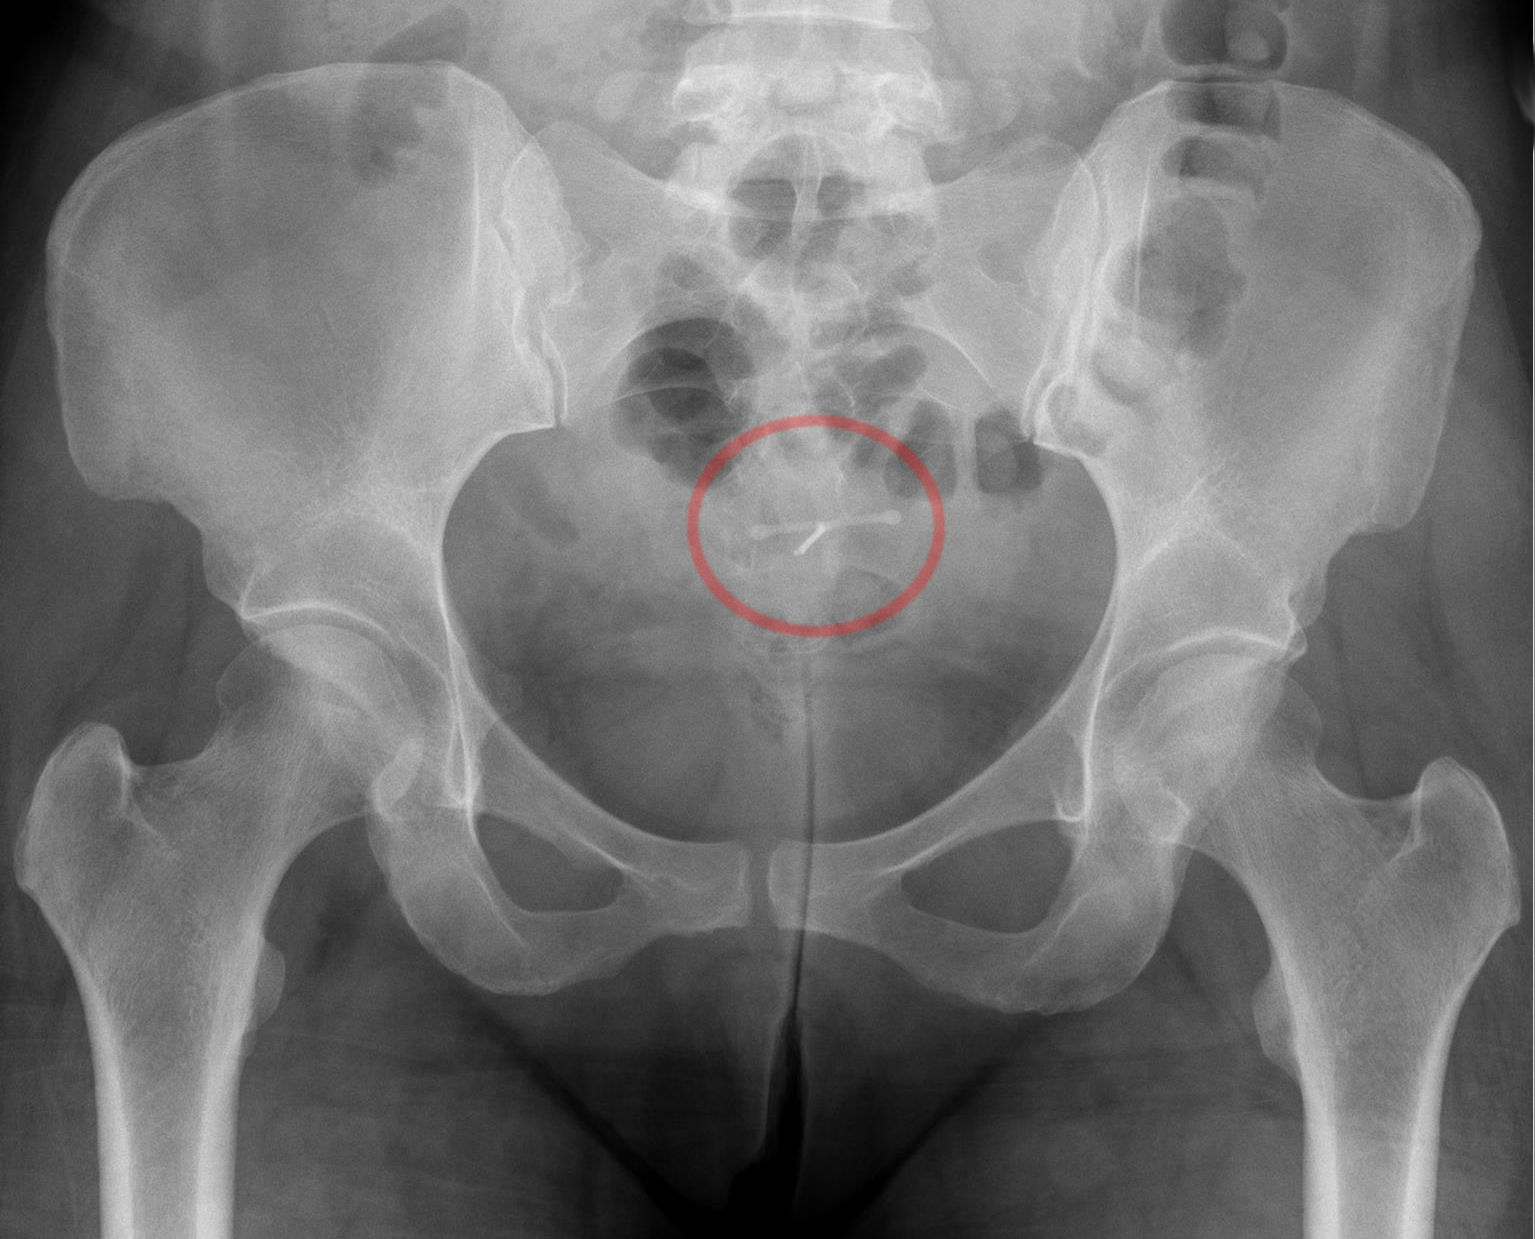

미레나는 프로게스토겐인 레보노르게스트렐을 포함하는 T자형 자궁 내 장치로, 피임 및 월경과다증, 자궁내막증, 자궁선근증, 만성 골반통, 월경곤란증, 빈혈, 자궁내막 증식증 등의 치료에 사용된다. 피임 효과가 매우 높고, 모유 수유 중에도 사용할 수 있으며, 최대 8년까지 효과가 지속된다는 장점이 있다. 삽입 후 불규칙한 출혈, 경련, 배출, 천공, 감염, 난소 낭종, 정신 건강 변화, 체중 증가, 두통 등의 부작용이 나타날 수 있으며, 임신, 자궁경부암, 유방암 등의 질환이 있는 경우에는 사용이 금지된다. 1970년대에 개발되어 1990년 핀란드에서 최초로 승인되었으며, 2007년 일본에서, 2014년 한국에서 사용이 시작되었다.

드물게 "실종된 코일"이 발생할 수 있는데, 이는 여성의 일상적인 검사에서 실을 느낄 수 없고 질경 검사에서 보이지 않을 때를 말한다.[60] 이 경우 초음파 검사를 통해 코일의 위치를 확인해야 한다.[61]

미레나는 T자형의 작은 플라스틱 조각으로, 프로게스틴의 일종인 레보노르게스트렐을 포함하고 있다.[71] 장치의 실린더는 약물 방출을 조절하는 막으로 코팅되어 있다.[72] 바이엘은 스카이라이를 영국에서 제이데스(Jaydess)라는 이름으로 판매한다.[73] 제이데스는 하루 6 µg을 방출하며 3년 동안 지속된다.[74] 이에 비해 경구 피임약은 150 µg의 레보노르게스트렐을 함유할 수 있다.[75] 호르몬 자궁 내 장치는 레보노르게스트렐을 직접 자궁으로 방출하므로, 그 효과는 전신적인 것보다는 대부분 파라크린 방식이다. 약물의 대부분은 자궁 내에 머물며, 소량만이 신체의 나머지 부분으로 흡수된다.[75]